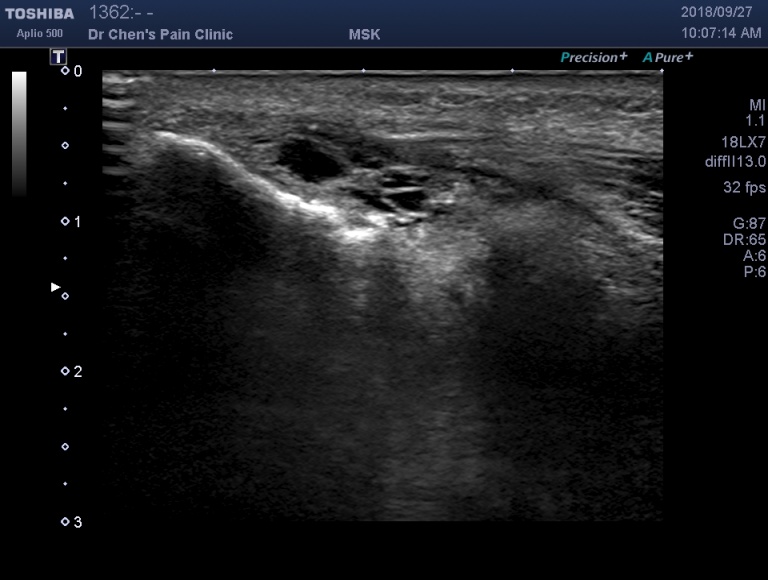

超音波診斷:動態測試

在動態測試中,可以清楚地看到肌腱裂開